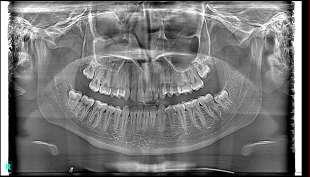

Elevate your 2D panoramic imaging with Deep-View AI, the revolutionary technology that enhances every detail with unmatched clarity and precision.

• Sharper images for superior diagnostics

• Enhanced contrast and depth to reveal critical details

• AI-powered optimization for faster, more efficient processing

Powered by advanced neural networks and deep learning, Deep-View AI processes X-VIEW 2D PAN and X-VIEW 3D PAN images with unparalleled accuracy. This cutting-edge technology unveils hidden anatomical

structures, optimizing every pixel in real time for precise and confident diagnostics.

Developed by Trident, this AI-driven enhancement is redefining the standards of dental imaging, setting a new benchmark for clarity and efficiency.